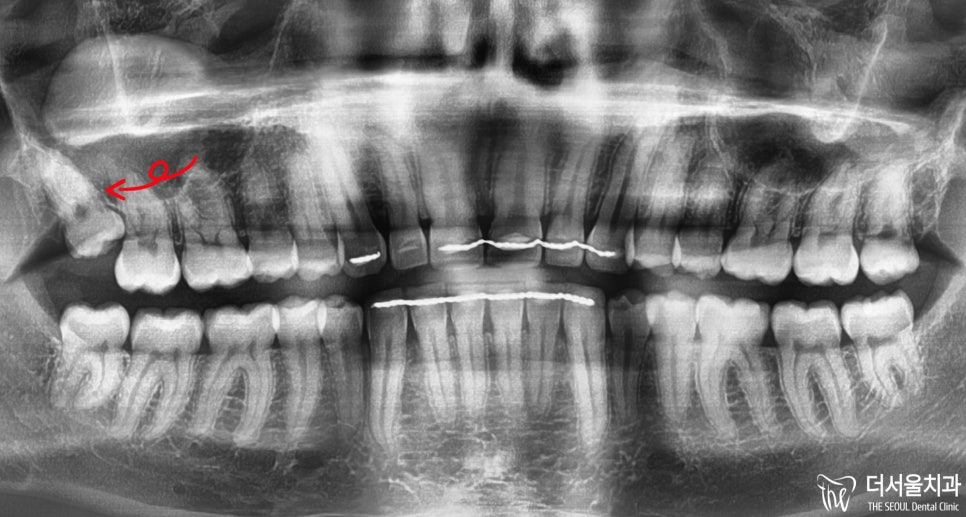

복정동 치과 사랑니 발치 노르웨이 외국인도 소개 받아온 극악의 난이도 (해외 진출 가능?)

안녕하십니까, 복정동 더서울 치과 쌍둥이 박현성 원장입니다. 오늘 소개해드릴 임상 증례는 노르웨이에서 오셨던 환자로 한국에 놀러온 겸 의료 기술이 […]